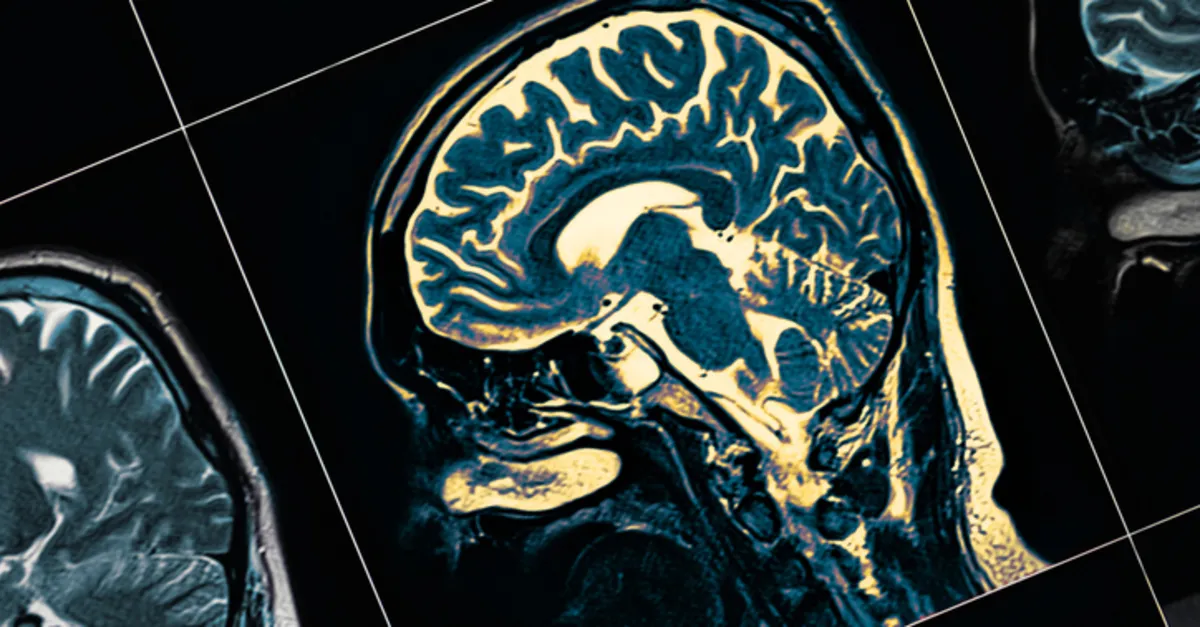

İlk olarak hastanın hikayesi,genel ya da nörolojik muayenesi yapılır. Daha sonra Beyin tomografisi ve beyin manyetik rezonans görüntülemeden faydalanılır.Bu testler sayesinde beyin tümörü yerleşimi, cinsi, hakkında ve büyüklüğü ile ilgili çabuk ve kısa zamanda bilgi alınır.Bazı beyin tümörleri teşhisinde ise beyin biopsisi gereklidir.